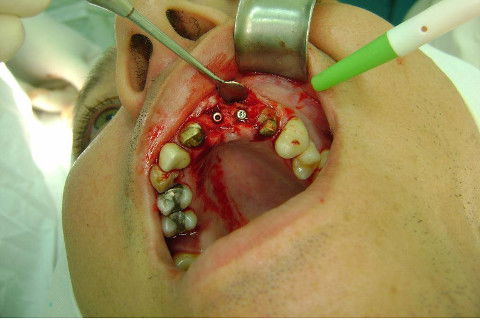

Cirurgia realizada hoje de manhã...No planejamento percebi medindo espessura do rebordo com especímetro que as medidas não estavam muito boas, ou o ideal, em torno de 4,5 a 5 mm ate´o terço médio do rebordo e melhorava no final, com 6 a 7 mm. Optei então por uma pequena expansão usando os expansores rosqueáveis. Aconteceu uma pequena fenestração na hora da fixação dos implantes, especialmente na região do 22 que fraturou o início da tábua óssea, mas não me preocupei porque não foi mais do que 2 mm de fratura em direção apical, o implante ficou infraósseo e com boa estabilidade (60 N no 21 e 40 N no 22). Esta fratura tb não deixou osso completamente solto, foi do tipo galho verde, deixei em posição e suturei normalmente. Só não fiz e nem estava planejado carga imediata mesmo, mais pelo motivo da oclusão inadequada do caso.

Fotos do caso